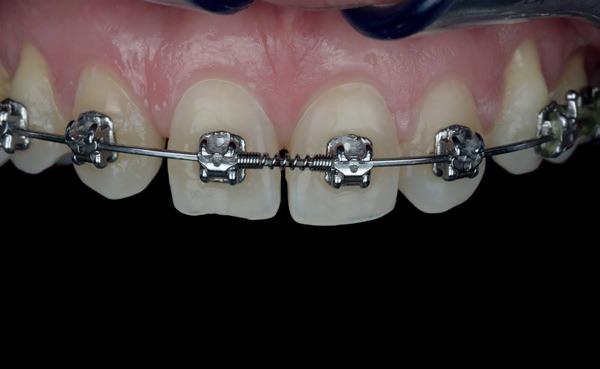

Een 47-jarige vrouw wordt aan het einde van het orthodontische traject door haar eigen tandarts naar mij verwezen voor een intake en eventuele behandeling. Bij mevrouw zijn elementen 12 en 22 afwezig. De 13 en 23 zijn gemesialiseerd. Haar eigen tandarts vraagt of ik het front met composiet kan restaureren om weer een harmonieuze glimlach te krijgen (Afbeelding 1).

Tijdens de intake wordt een complete lichtfoto status gemaakt om de positie van de elementen goed in kaart te brengen en een behandelplan op te kunnen stellen. Op de close-up foto van het bovenfront (afbeelding 2) zien we dat er sprake is van slijtage aan element 11. Elementen 12 en 22 zijn afwezig en elementen 13 en 23 zijn gemesialiseerd. Tussen element 11 en 13 is er sprake van een diasteem. Dit diasteem is niet aanwezig aan de andere zijde (afbeelding 3).

Dit zorgt voor een lastige situatie, omdat bij het sluiten van dit diasteem (dit is de wens van de patiënt) elementen 13 en 11 breder zullen worden dan elementen 21 en 23. Dit is één van de redenen waarom ik patiënten altijd graag aan het einde van het orthodontist traject wil zien. Op dat moment is het nog mogelijk om kleine wijzigingen door te voeren, voordat de beugel definitief wordt verwijderd. Na de intake stuur ik een terugrapportage naar de orthodontist waarbij ik vraag om de elementen zo te positioneren dat de ruimte beter verdeeld is.

Ik zie mevrouw een aantal weken later terug voor evaluatie (afbeelding 4). Er is een klein centraal diasteem ontstaan en daardoor is het diasteem tussen de 11 en 13 ook kleiner geworden. Tussen de 21 en 23 is geen diasteem aanwezig (afbeelding 5), waardoor er hoogstwaarschijnlijk wel iets breedte verschil zal zijn tussen de linker- en rechterzijde.

Met composiet wordt een snelle mock-up gemaakt om te beoordelen of ik in deze situatie goed kan uitkomen met de ruimte, of dat we wellicht de elementen nog meer moeten verplaatsen (afbeelding 6). Mevrouw is zeer tevreden met de snelle mock-up en daarom wordt besloten dat de orthodontische behandeling afgerond kan worden. Eventuele verschillen in breedte kunnen we proberen optisch zoveel mogelijk te maskeren.

Nadat de vaste apparatuur verwijderd is (afbeelding 7 en 8), zie ik mevrouw voor het maken van een afdruk/scan ten behoeve van een wax-up. Aangezien ik in deze casus wil werken met de injectietechniek, is een wax-up noodzakelijk.

1: Glimlach foto om de positie van de elementen ten opzichte van de lippen te beoordelen.

2: Close-up foto van de voortanden in de bovenkaak.

3: Occlusale foto om de positie van de elementen en de diastemen te beoordelen.

4: Situatie na orthodontische aanpassingen.

5: Occlusale foto om de nieuwe positie van de elementen te beoordelen.

6: Snelle mock-up met composiet om te bepalen of de huidige stand van de elementen de ruimte biedt om de elementen in de juiste vorm op te bouwen.

7: Glimlach foto na verwijderen van de vaste apparatuur.

8: Close-up foto van voortanden na verwijderen vaste apparatuur.